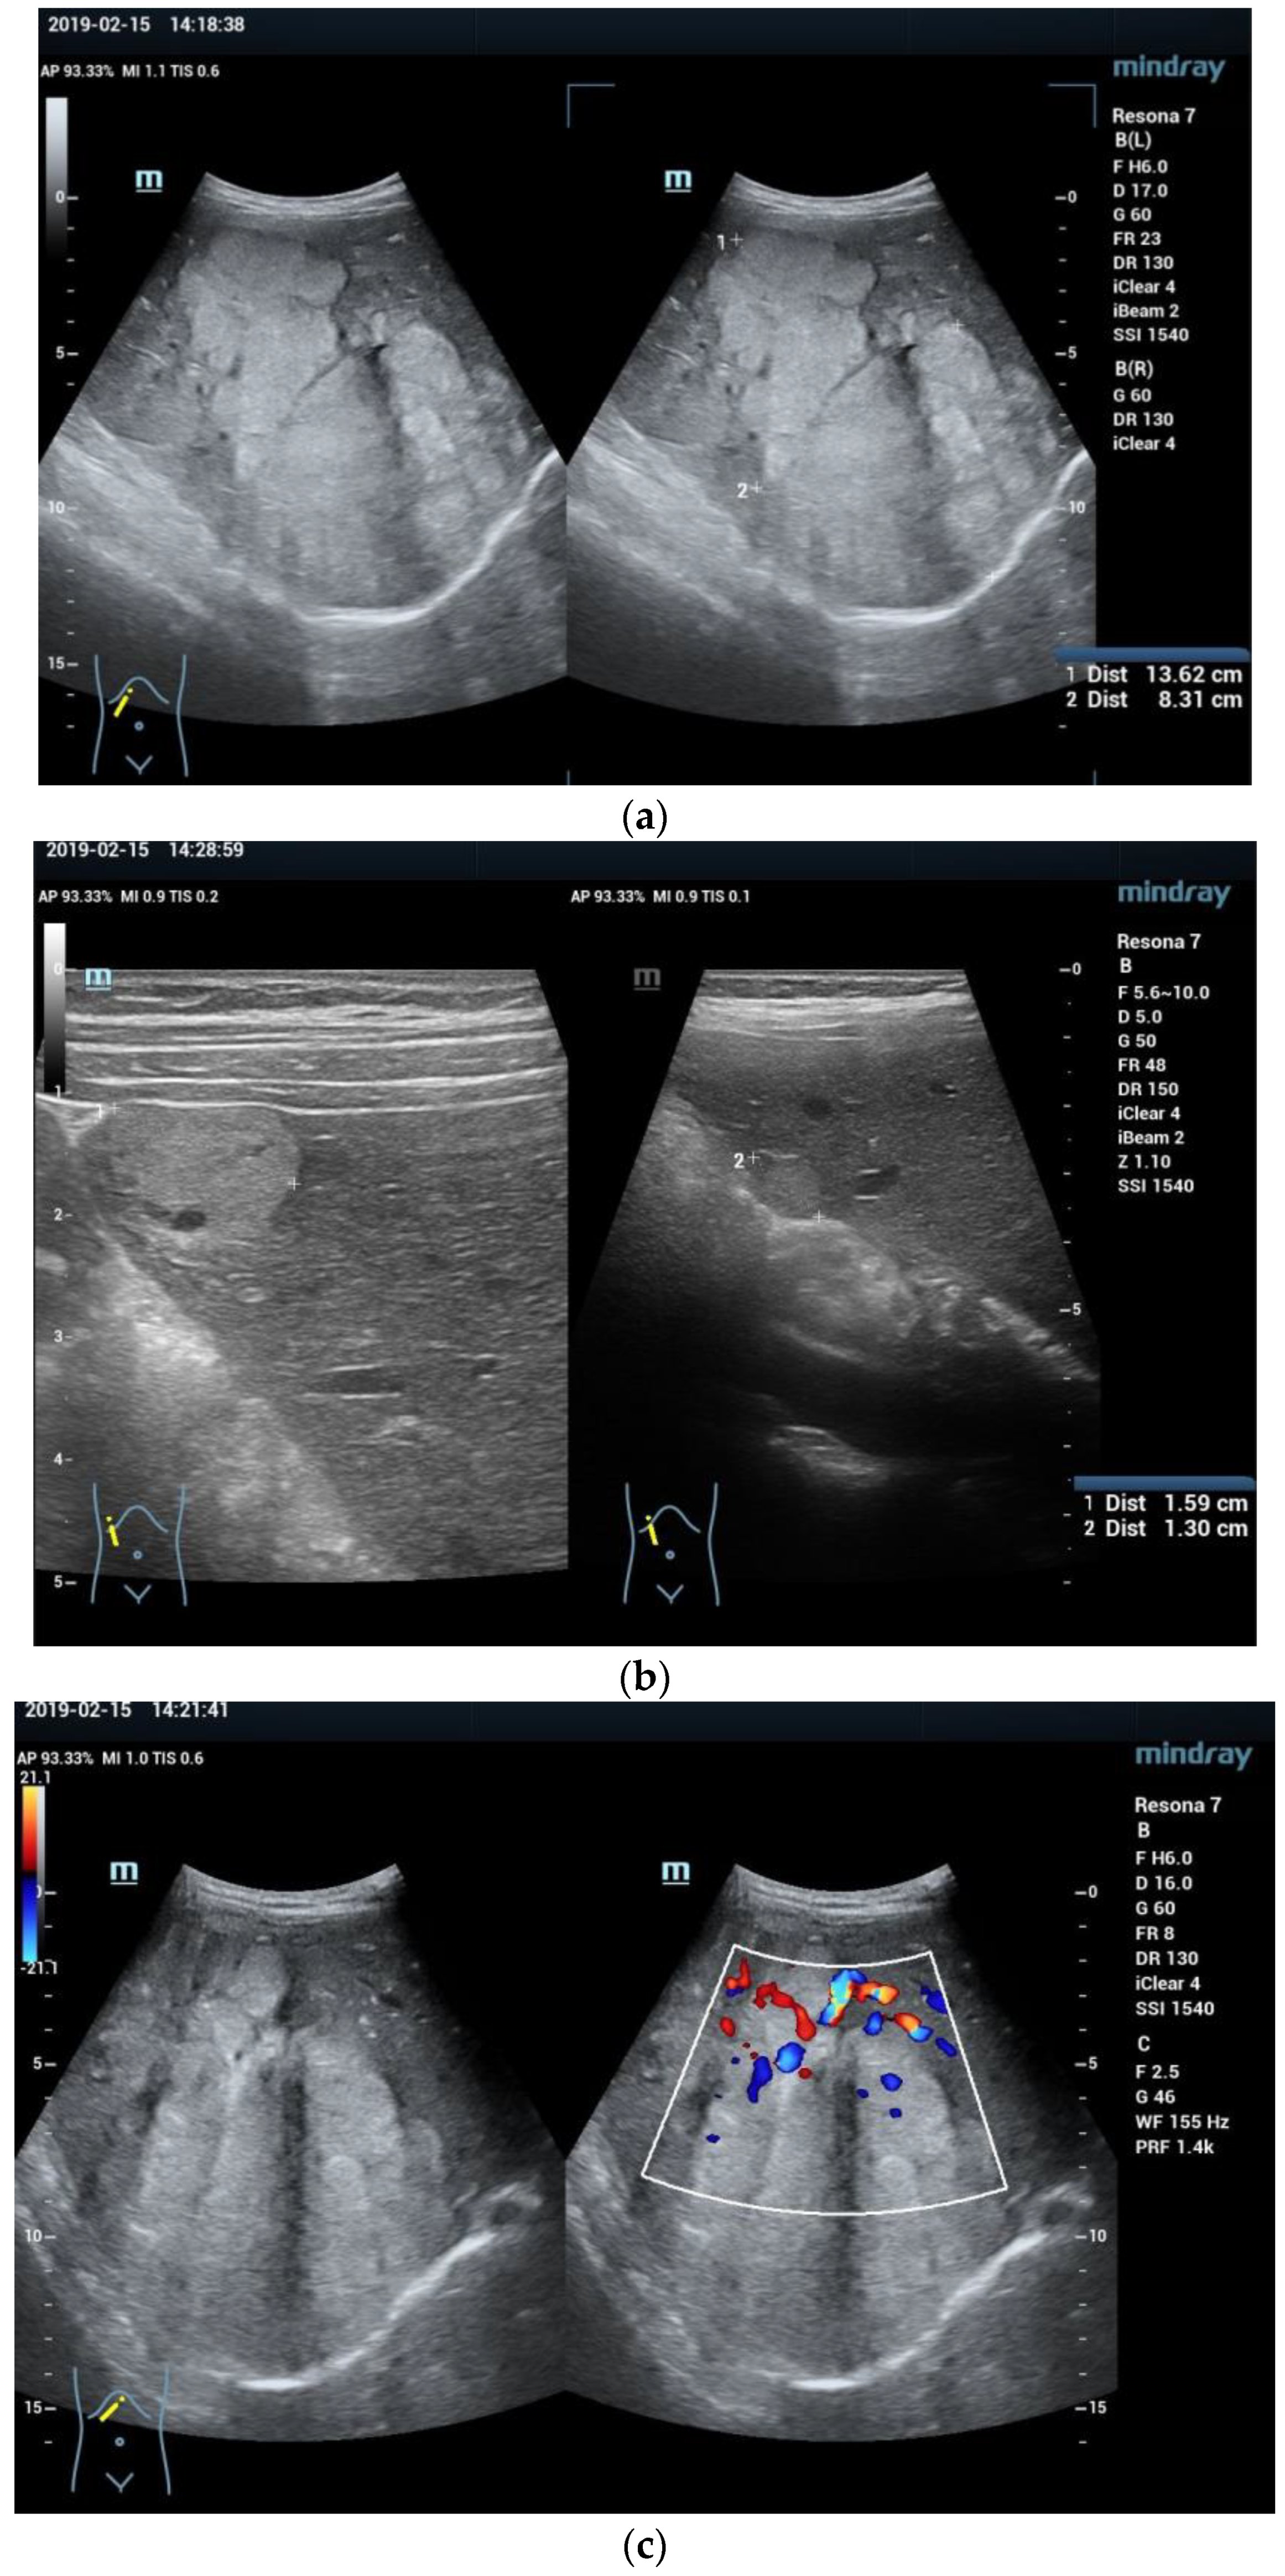

- Zhuang, H.; Peng, Y.L.; Chen, T.W.; Jiang, Y.; Luo, Y.; Zhang, Q.; Yang, Z.G. The comparison of grey-scale ultrasonic and clinical features of hepatoblastoma and hepatocellular carcinoma in children: A retrospective study for ten years. BMC Gastroenterol. 2011, 11, 78. [Google Scholar] [CrossRef] [PubMed]

- Pan, F.S.; Xu, M.; Wang, W.; Zhou, L.Y.; Xie, X.Y. Infantile hepatic hemangioendothelioma in comparison with hepatoblastoma in children: Clinical and ultrasound features. Hepat. Mon. 2013, 13, e11103. [Google Scholar] [CrossRef]

- Anupindi, S.A.; Biko, D.M.; Ntoulia, A.; Poznick, L.; Morgan, T.A.; Darge, K.; Back, S.J. Contrast-enhanced US Assessment of Focal Liver Lesions in Children. Radiographics 2017, 37, 1632–1647. [Google Scholar] [CrossRef]

- Wang, G.; Xie, X.; Chen, H.; Zhong, Z.; Zhou, W.; Jiang, H.; Xie, X.; Zhou, L. Development of a pediatric liver CEUS criterion to classify benign and malignant liver lesions in pediatric patients: A pilot study. Eur. Radiol. 2021, 31, 6747–6757. [Google Scholar] [CrossRef] [PubMed]